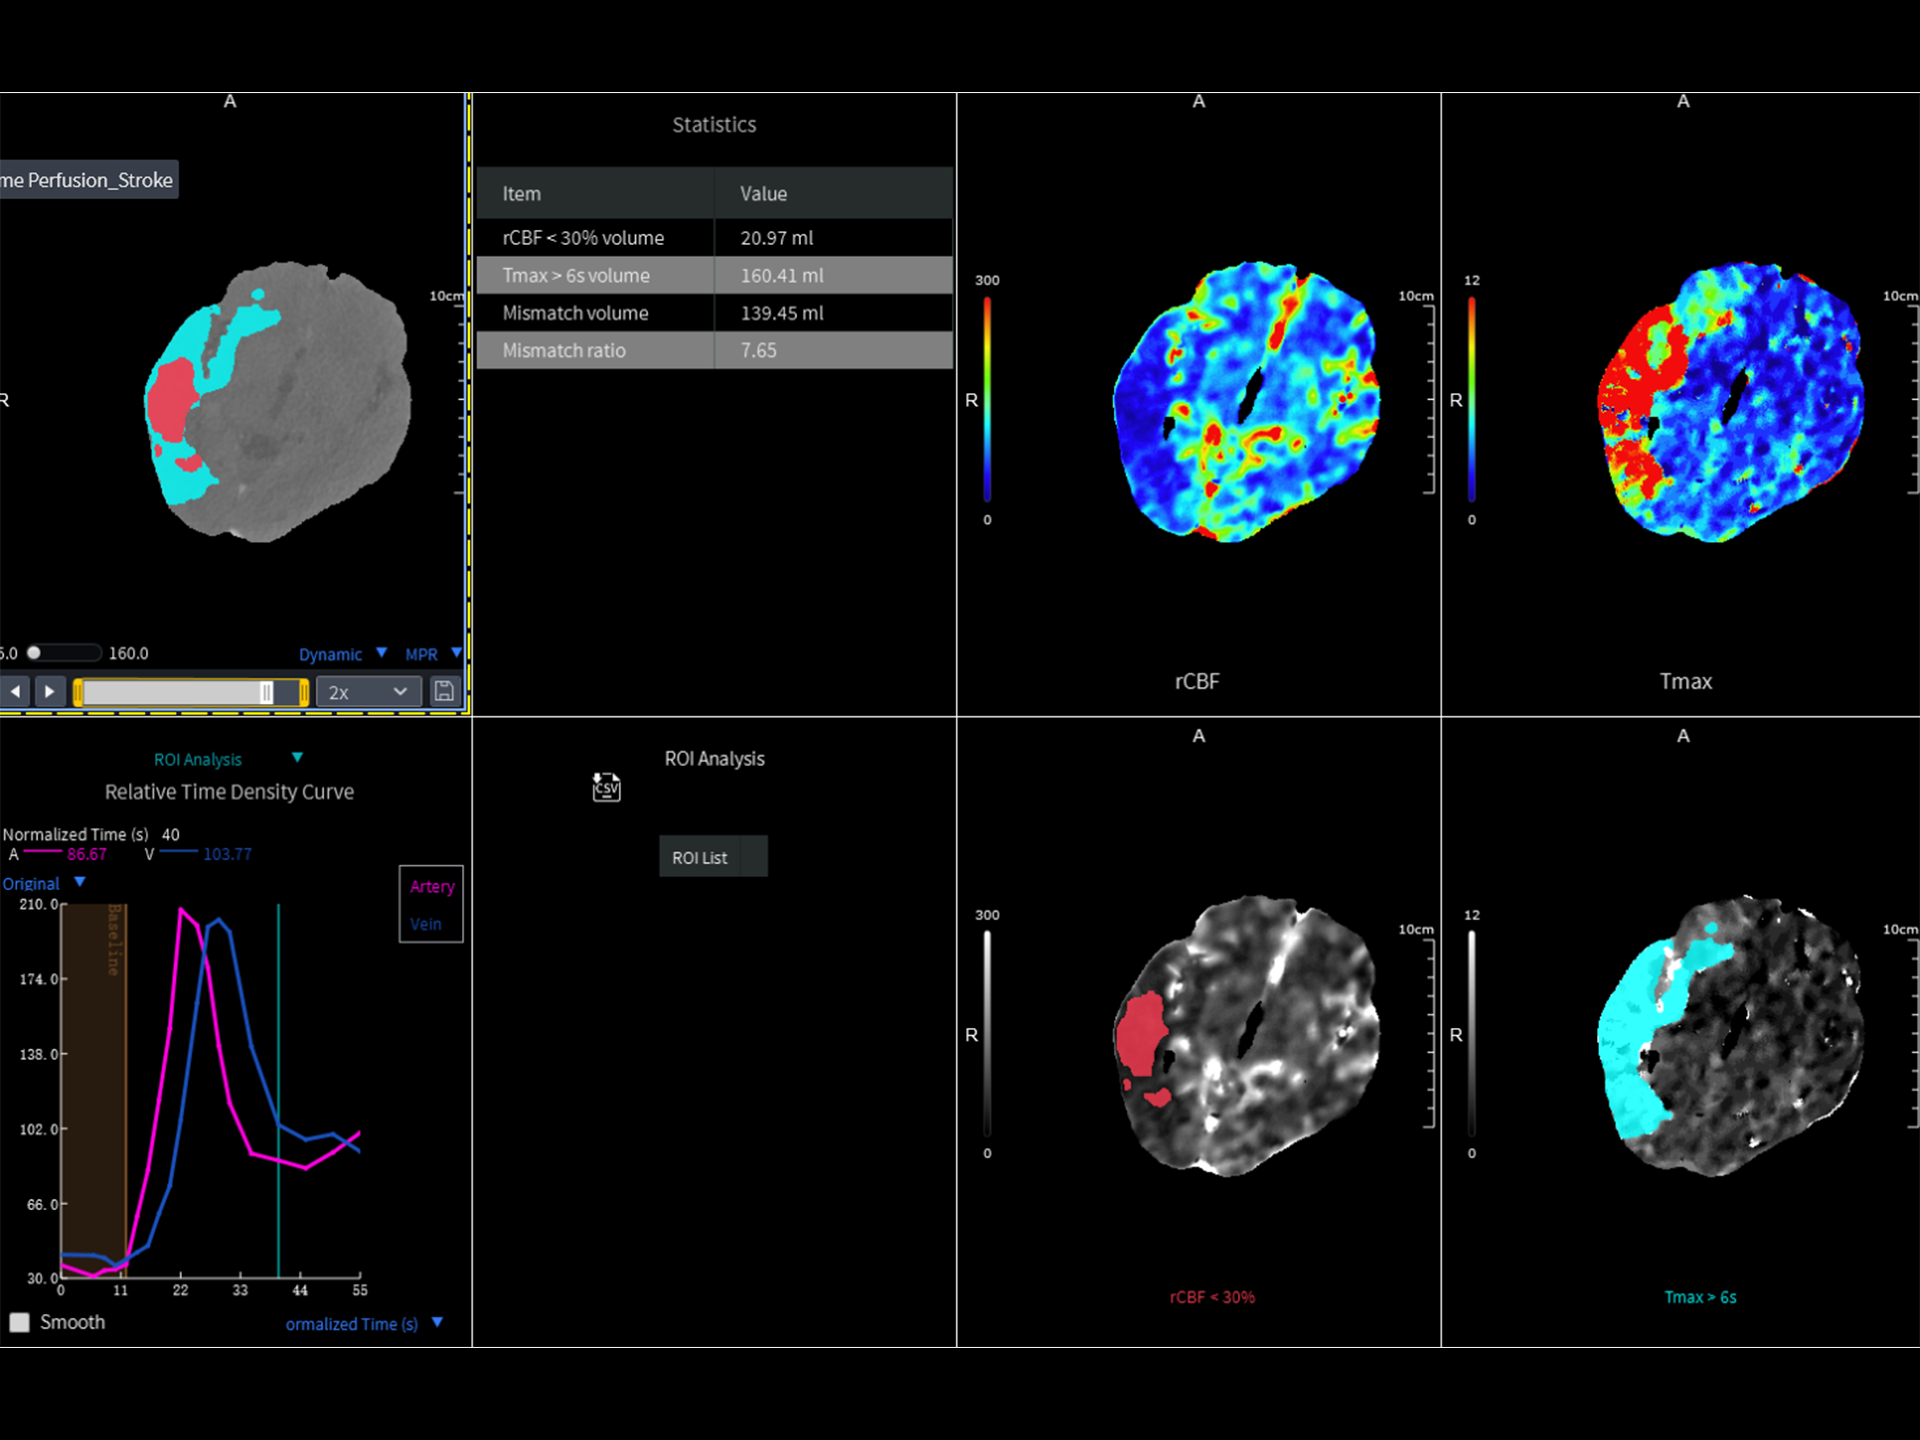

uCT 868 搭载联影最新一代 uSense 人工智能平台,将智能化深度融入 CT 扫描全流程,从感知细微生理运动到精细结构探测,再到多场景诊疗优化。以 AI 为核心驱动力,uSense 重塑成像各环节,打造高效、高清的智慧扫查体验。在心脏成像领域,uSense 结合宽体探测器、心脏专研AI重建算法与AI冠脉运动追焦技术,在保持低剂量的同时,有效抑制运动伪影,精准呈现软斑块、混合型斑块及支架细节,助力冠脉成像惠及更多患者。针对多科室疾病临床应用场景,uSense 平台提供全方位的智能解决方案:包括头部运动伪影智能校正、金属植入物伪影抑制、扫描视野扩展等先进算法。这些创新技术使 uCT 868 能够构建覆盖全场景的智能诊疗体系,持续拓展 AI 赋能医学影像的边界。

在高端CT系统中,对速度与图像质量的要求早已不局限于常规检查,更延伸至复杂、挑战性更高的临床场景。临床常见的急性病症覆盖多个专科领域,包括心血管、神经系统以及创伤急症。这些领域疾病通常起病突然、进展迅速,对成像速度、覆盖范围、图像质量及诊断效率提出极高要求。

作为高端CT解决方案平台,uCT 868 凭借高速扫描能力、宽体探测器、AI驱动重建算法和智能工作流,能够从容应对上述急症场景下的多部位、多模式联合检查需求。不论是冠脉、主动脉与肺动脉的一站式成像,还是卒中的快速识别,亦或是全身创伤评估中的快速定位与精细结构显示,uCT 868 均能以高速、清晰、低剂量的成像表现,助力临床在关键时刻做出快速而准确的诊断判断,赢得宝贵救治时间。